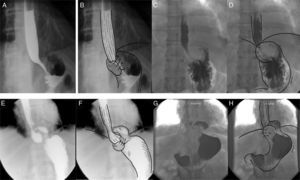

Síntomas esofágicosA. Disfagia. La disfagia postoperatoria tiene alta incidencia (76%), en general es de leve intensidad y se resuelve en las primeras semanas. Hasta un 20% persistirá durante un año y entre el 5 y el 8% por más tiempo. Si la disfagia es persistente, es recomendable realizar un esofagograma con contraste5 (fig. 2). La presencia preoperatoria de disfagia, el retraso en el vaciamiento gástrico, una menor presión de amplitud en el esófago distal, la presencia de hernia hiatal y la mayor presión basal en la unión esofagogástrica (UEG) son predictores de disfagia posquirúrgica21,22.

Evaluación radiológica con contraste en diferentes escenarios de la funduplicatura. A) Trago de bario con proyección antero-posterior de la funduplicatura tipo Nissen 360° en donde el fondo del estómago está envolviendo el esófago distal en forma completa. B) Trago de bario con esquema sobrepuesto. C) Trago de bario con proyección antero-posterior de la funduplicatura tipo Nissen 180° en donde el fondo envuelve parcialmente el esófago distal. D) Trago de bario con esquema sobrepuesto. E) Trago de bario con proyección antero-posterior de una funduplicatura tipo Nissen 360° con migración tipo i, observándose la herniación por arriba y la UEG por debajo del diafragma. F) Trago de bario con esquema sobrepuesto. G) Trago de bario con proyección antero-posterior de una funduplicatura tipo Nissen 180° con migración tipo i, observándose la herniación por arriba y la UEG por debajo del diafragma. H) Trago de bario con esquema sobrepuesto.

Tomado de Raeside et al.34.